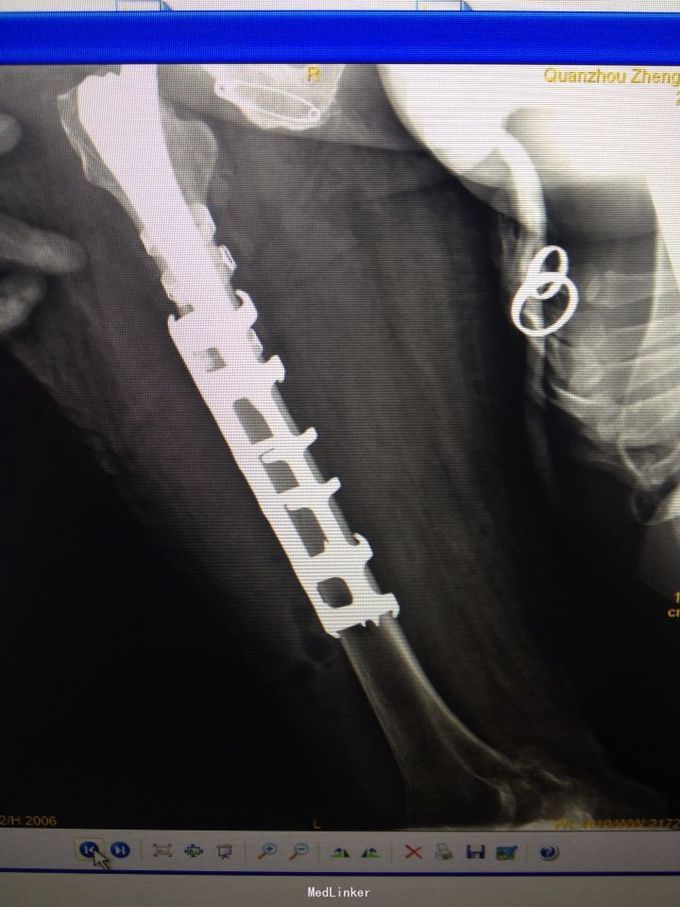

右股骨头置换术后股骨假体周围骨折(B3) 行右人工股骨头置换术后假体周围骨折切开复位记忆合金钢板+钛缆绑带固定术

术后3个月随访效果佳